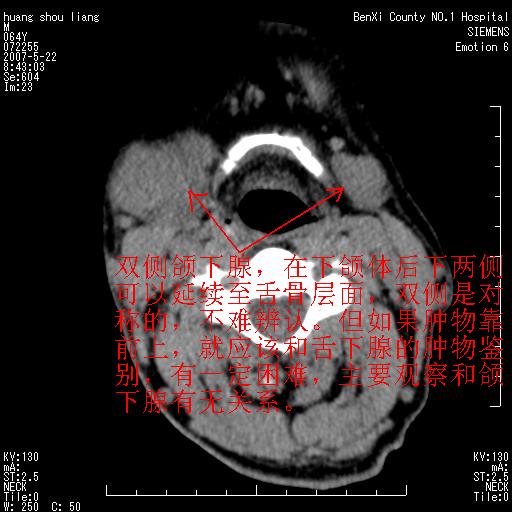

对不起大家,可能是片子发太多有点乱,正常腮腺在下颌角的外侧,颌下腺在下颌体的中部内侧,本例在下颌角内侧偏下,和腺体一点关系都没有,从vrt和mpr上可以很明显看出来,再者肿块是好多粘连在一块的,大家在仔细看看,左侧可能也是吧,我还是考虑为肿大的淋巴结融合在一块,但性质??????

画个图共同讨论一下解剖关系。